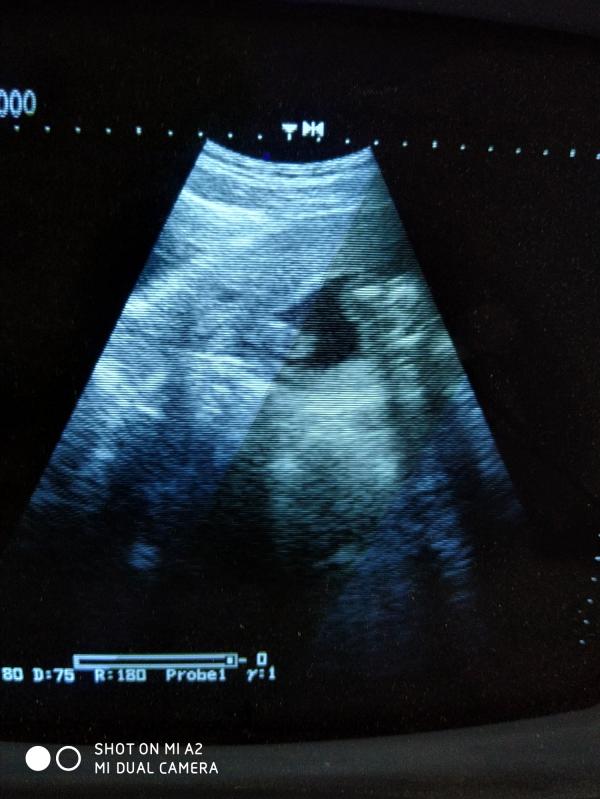

Ура, на Новый год мечты сбываются🤩🎉. 31 декабря на УЗИ показался мальчишка👼, а 1 января почувствовала шевеления и крошечные пиночки👣. Счастью нет предела💃

Да, ровно 17 недель. Надеюсь врач не ошиблась, хотя вроде всё чётко видно)